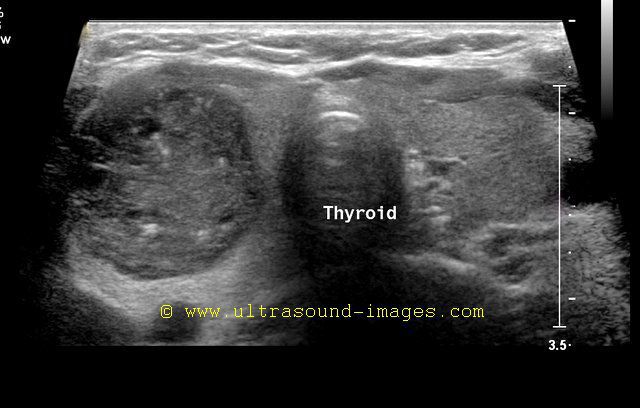

Sonography of the thyroid in this 1 yr. old female child revealed congenital absence of the entire thyroid. Note the empty fossae where the right and left lobes would normally lie. The carotid artery and jugular vein of both sides are seen in the color doppler images. These ultrasound and color doppler images suggest congenital agenesis of the thyroid.